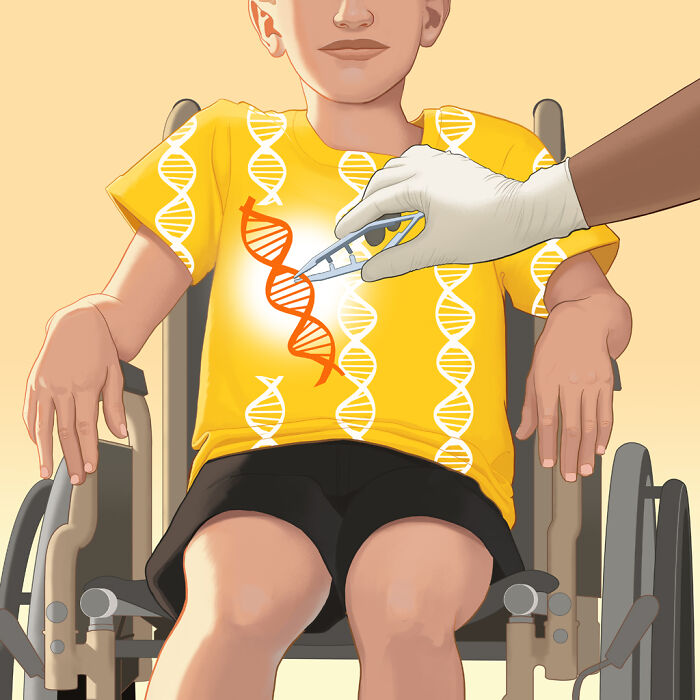

Genetics